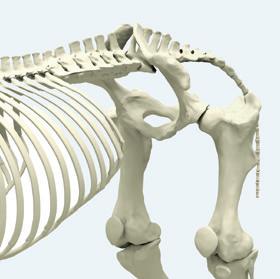

Annie Lambert talks to Dr. Michael Manno about dilemmas the Sacroiliac joint can pose and how to deal with these.

Computed tomography (CT) helps veterinarians make diagnoses and trainers make decisions. CT scanners take hundreds of x-ray images rotating around the target and create an exact 3D digital rendering. The diagnostic power is in the ability to scroll through the 3D rendering slice by slice, at any angle you choose.

• The neck: It is shocking how many abnormalities are visible with 3-dimensional imaging of the neck. Nerve compression is visible even when it comes from the side; previously undiagnosable with regular radiographs.

• Surgery: CT guidance enables accurate fracture reconstruction and precise placement of screws in difficult locations.

Image detail is far superior with fan beam; the main reason MidAtlantic Equine moved to it from the robotic CT. Most fan beam CT units are small and require general anesthesia. The CT scanner at Mid-Atlantic Equine is a Canon large bore CT mounted on a computer controlled platform, allowing true CT imaging in a standing horse (foot to forearm or gaskin, nose to base of the neck C5/6 or 6/7). Under anesthesia imaging of elbows, shoulders, chest, thoracic spine, back, pelvis, SI, hips and stifles can be obtained.